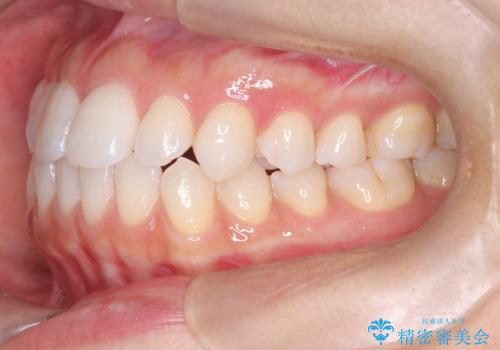

「歯を抜かずに、たった10ヵ月。」目立ちにくい大人の矯正

その結果、約10ヵ月という比較的短期間で歯列と咬み合わせが整い、機能面・審美面ともに良好な結果を得ることができました。